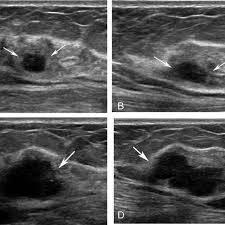

On ultrasound it will be hypoechoic with spiculations radiating away from the nipple. Radiographic features ultrasound malignant characteristics (with positive predictive values) Ultrasound imaging allows better evaluation of the status of the axillary lymph nodes in patients with ibc, an important step in determining extent of disease prior to initiation of chemotherapy. Is the abnormal enlargement of rudimentary male breast tissue. You might get a breast ultrasound: Breast cancer is among the most common causes of cancer deaths today, coming fifth after lung, stomach, liver and colon cancers. Many cancers are not visible on ultrasound. Breast cancer usually makes or presents as a mass or tumor or a lump. This type of cancer also changes the appearance of your breasts. Papillary dcis, a special variant, will show up as matter within the ducts, like a clog within a pipe. It is the most common cause of cancer death in women. in 2005 alone, 519 000 deaths were recorded due to breast cancer. this means that one in every 100 deaths worldwide and almost one in every 15 cancer deaths were due to breast cancer. Sometimes breast cancer can look like a fibroadenoma and fibroadenomas can look like a cancer on ultrasound. Many calcifications seen on mammography cannot be seen on ultrasound.

Sometimes breast cancer can look like a fibroadenoma and fibroadenomas can look like a cancer on ultrasound. Some early breast cancers only show up as calcifications on mammography. Breast cancer usually makes or presents as a mass or tumor or a lump. Rather, the right breast is seen as smaller than the left breast. On ultrasound, a breast cancer tumor is often seen as hypoechoic, has irregular borders, and may appear spiculated.

You might not need any further tests if everything looks normal. It can help your healthcare provider find breast problems. When is breast ultrasound used? If your breast tissue is too dense for a mammogram. This test is often used when a change has been seen on a mammogram or when a change is felt. Papillary dcis, a special variant, will show up as matter within the ducts, like a clog within a pipe. You may notice dimpling or pitting, and the skin on your breast. On ultrasound, a breast cancer tumor is often seen as hypoechoic, has irregular borders, and may appear spiculated. This breast cancer ultrasound image shows changes related to breast cancer that are not seen as microcalcifications or a mass or lump. Some early breast cancers only show up as calcifications on mammography. If a solid lump shows on the scan you might need to have. A rash isn't the only visual symptom of inflammatory breast cancer. Ultrasound is frequently used to evaluate breast abnormalities that are found with screening mammography or diagnostic mammography or during a physician performed clinical breast exam.ultrasound allows significant freedom in obtaining images of the.

Breast ultrasound is an imaging test that uses sound waves to look at the inside of your breasts. Ultrasounds are usually quick and most don't require special preparation. If your breast tissue is too dense for a mammogram. When is breast ultrasound used? Not all suspicious breast lesions will direct in appearance and ultrasound diagnosis. This high amount of echo results in a bright white spot appearing on the ultrasound image. You can get dressed straight after the ultrasound. Ibc is a rapidly progressive, aggressive form of breast cancer associated with a low overall survival rate. On ultrasound, a breast cancer tumor is often seen as hypoechoic, has irregular borders, and may appear spiculated. In the table the differences in ultrasound appearances are listed. Is the abnormal enlargement of rudimentary male breast tissue. This test is often used when a change has been seen on a mammogram or when a change is felt. Breast cancer usually makes or presents as a mass or tumor or a lump.